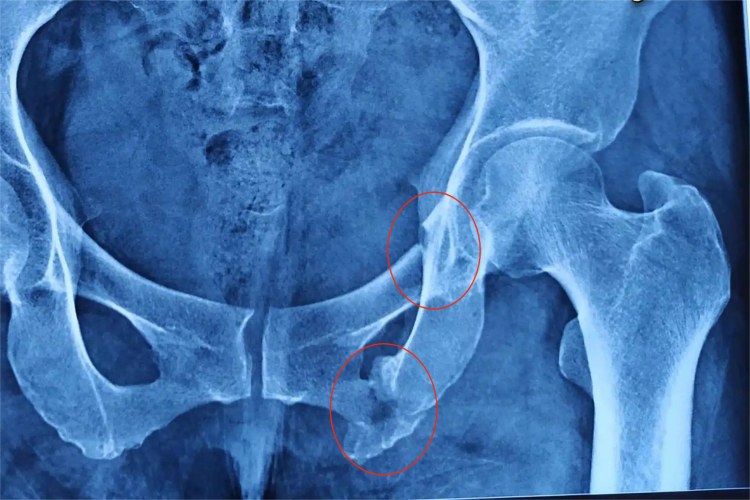

左侧耻骨上下支骨折无固定位置,可发生在左侧骨盆耻骨上下支的任何部位,大致位于左侧腹股沟。左侧耻骨上下支骨折后,局部可出现肿胀、疼痛、压痛,骨盆挤压及分离试验时疼痛加重,尤其在左侧腹股沟区域。行X线检查见耻骨上下支骨质断裂、错位,骨盆前环轮廓变形,骨折端可无移位。